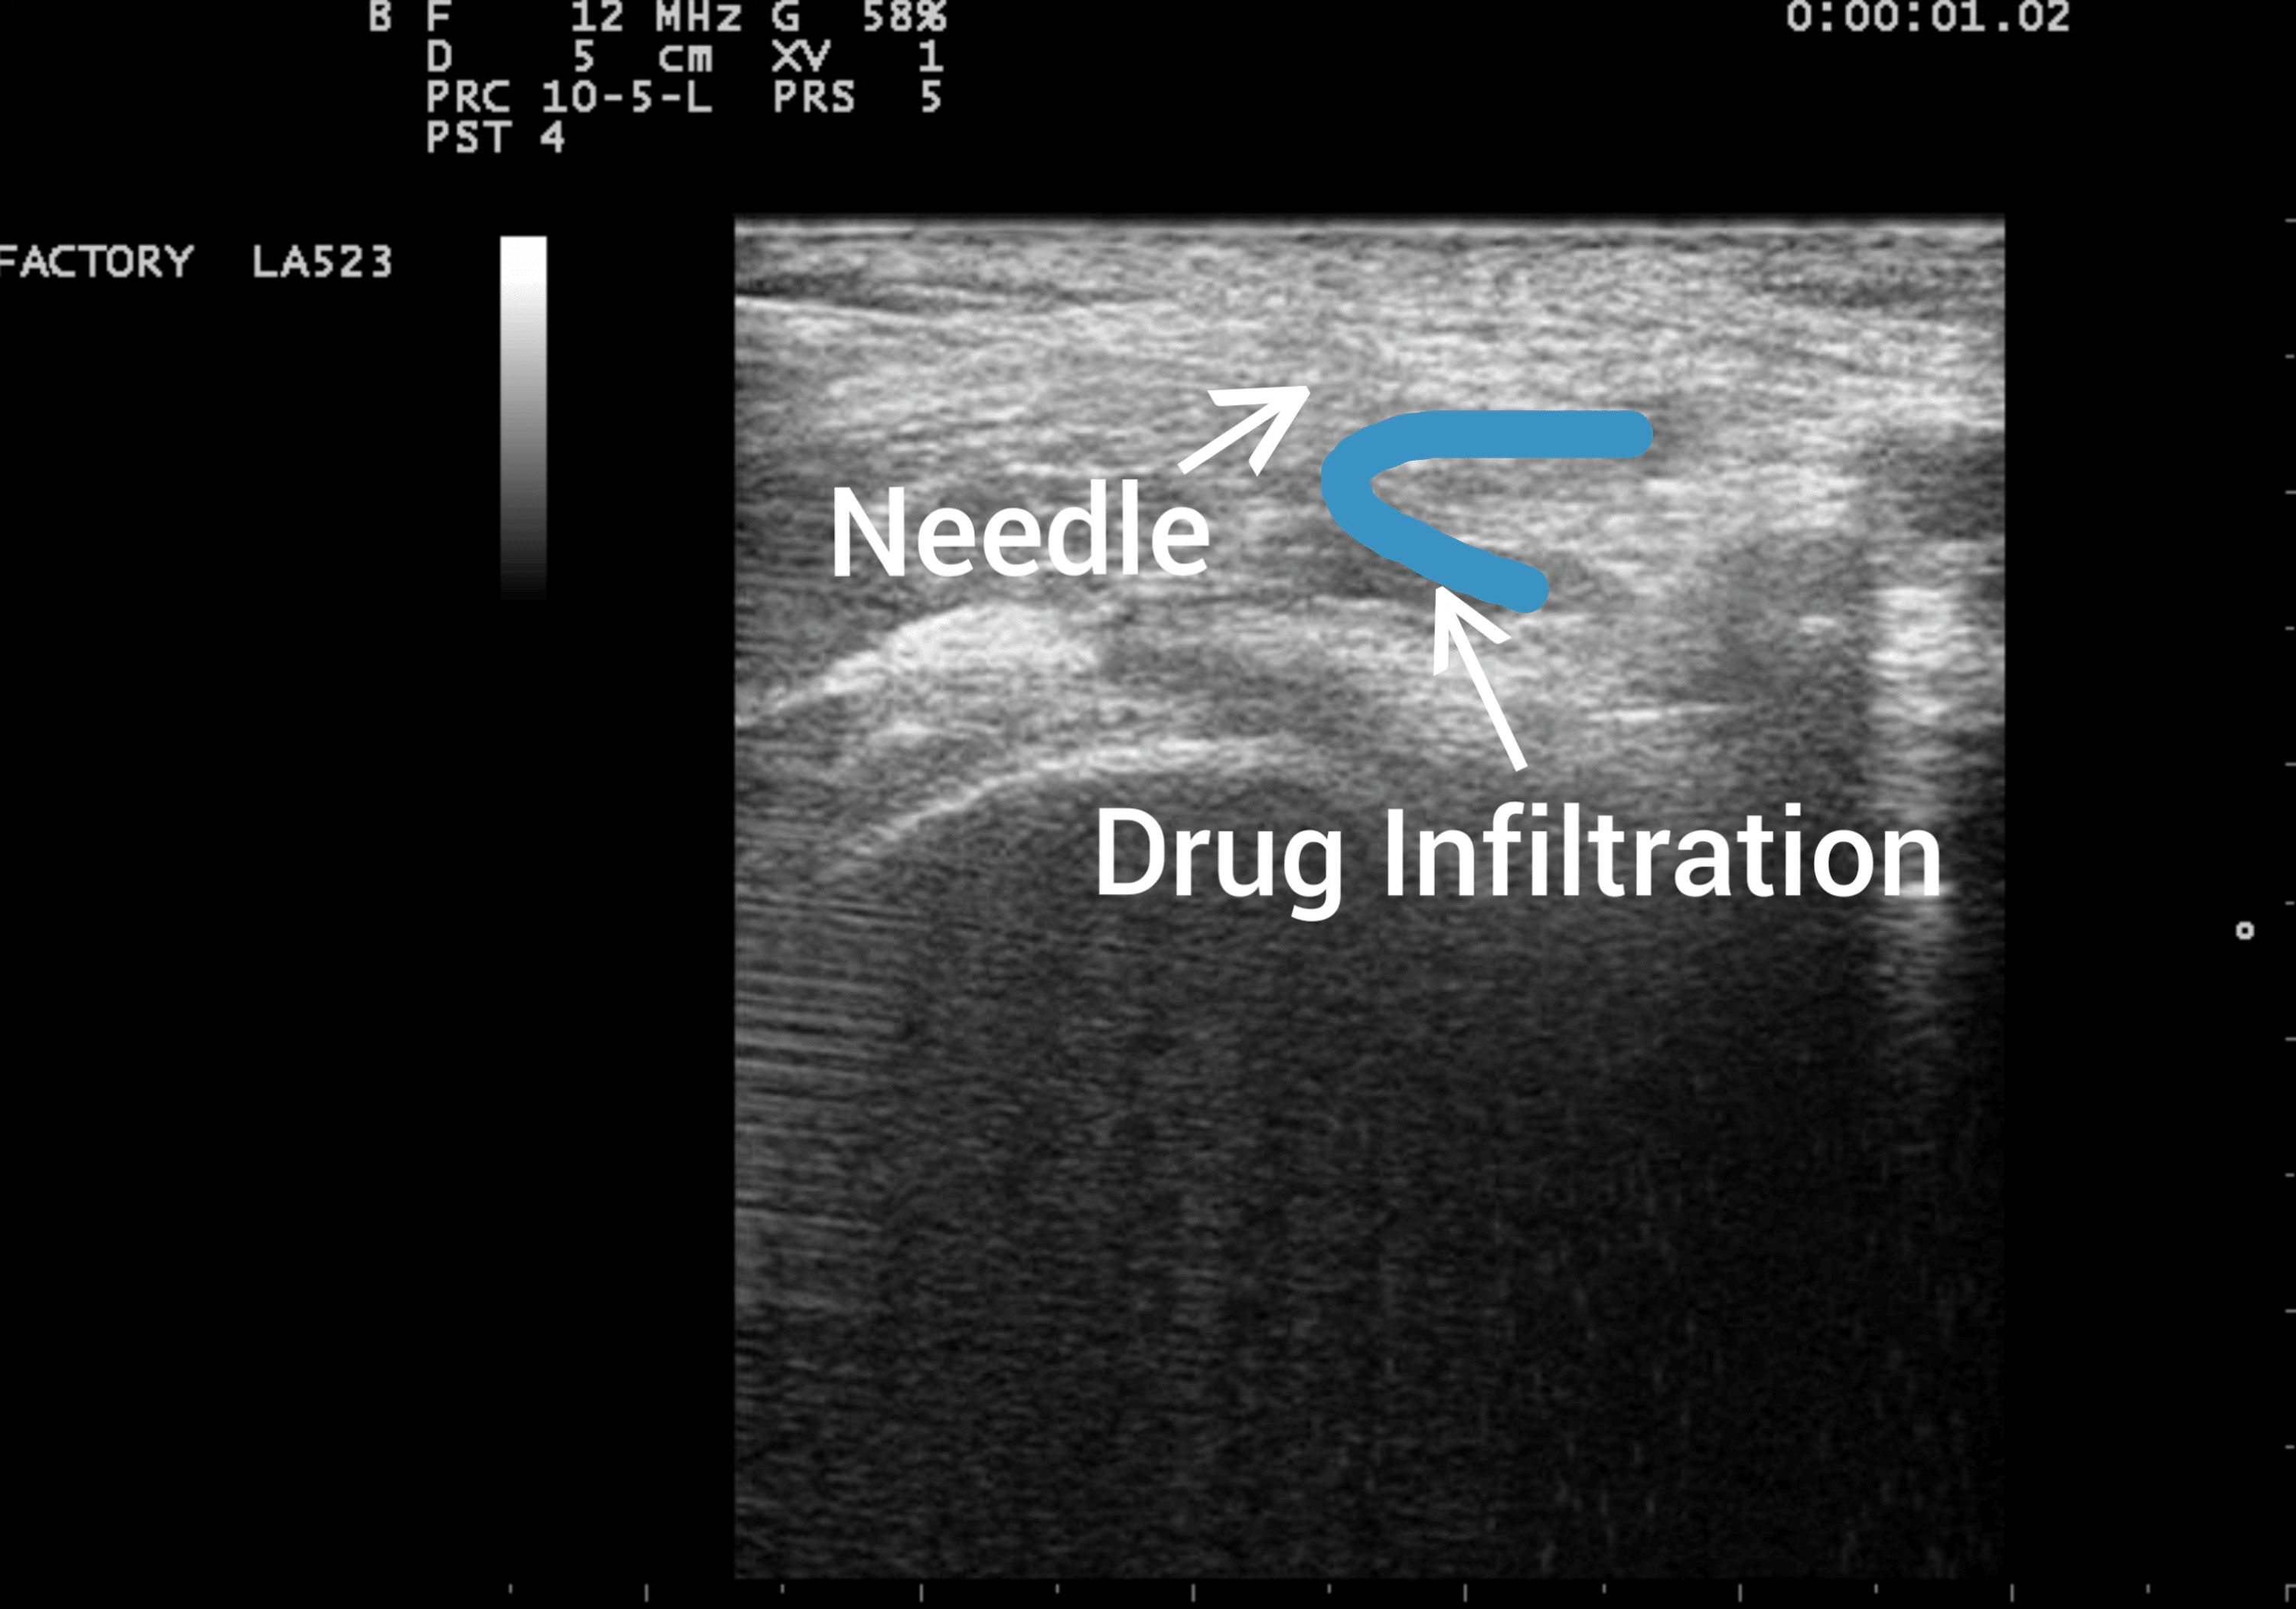

Transverse sonogram of the femoral nerve after injection of a local Femoral Nerve Block Local Anesthetic Dose    continuous femoral nerve blocks:  complications of femoral nerve block include vascular puncture, femoral nerve compression by a hematoma, diffusion of the local anesthetic solution.   the type of local anesthetic given, concentration, and. Regional anaesthesia of the femoral nerve provides rapidly effective, medium duration anaesthesia for femoral. Surgeons use femoral nerve blocks to provide regional anesthesia for several. Femoral Nerve Block Local Anesthetic Dose.